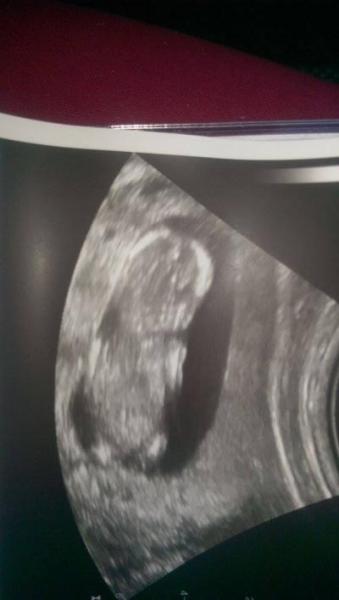

Haallo und guten Morgen. :) Heute morgen hatten wir um 9.30 Uhr einen Termin zum Baby-Tv. Und siehe da: Herz schlägt, das Wunder lag auf der Seite mit dem Gesicht zu uns gedreht und winkte und zu, also ob es sagen wollen würde "Haaaallo, hier bin ich." :) Das war ein wunderbares Gefühl. SSL liegt bei 6,5cm und entspricht wohl genau 13+2 Tage. Da befinde ich mich heute ja nun auch. Mein Freund und ich haben dann heute ein bisschen diskutiert was es wird und haben das US-Bild auch gleich meinem Papa gezeigt, der sagte "DAS WIRD EIN MÄDCHEN! ICH LAG NOCH NIE FALSCH" und sich gefreut hat wie ein Schneekoenig. :) Er wuerde sich natuerlich auch ueber einen Jungen freuen. Ich finde auch, dass es eigentlich mehr wie ein Maedchen aussieht, aber ich werde mich nicht festlegen. 14. Woche ist dafuer eigentlich noch zu frueh. Habt ihr da schon ne Meinung zu? Liebe Grueße und einen sonnigen Tag :)

Glückwunsch, das sieht ja hübsch aus. Na mal sehen, ob sich das mit dem Mädchen noch bestätigt.